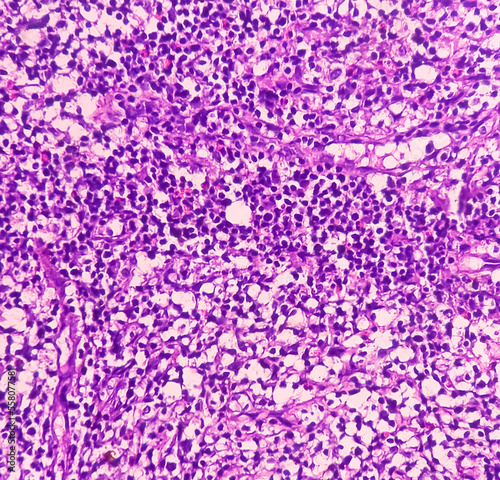

Mikrofotografi - Plakater, Poster, Billeder på lærred